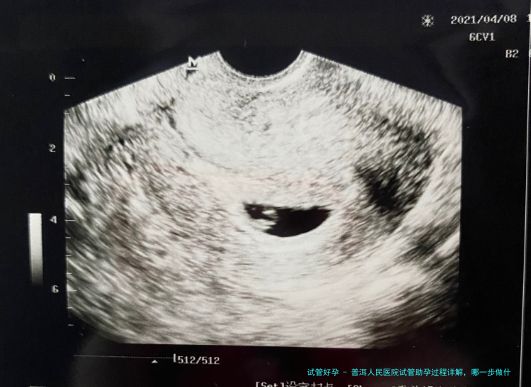

1. 前期检查:男性检查主要以精液检查为主,女性检查主要以卵巢、输卵管、子宫、激素水平等检查为主;2. 促排卵:医生根据患者的身体情况和卵巢储备情况等,制定一套适合患者情况的方案,并应用此方案进行促排卵治疗;3. 取卵、取精:当排卵监测显示卵泡发育达标时,医生会安排女方进行取卵手术,同时男方也需要进行取精手术;4. 胚胎培养:精子和卵子取出后,送往胚胎实验室进行受精,3-5天后可培育成胚胎;5. 胚胎移植:一般在3-5天后行移植手术,将胚胎放置到母体宫腔内。Tips: